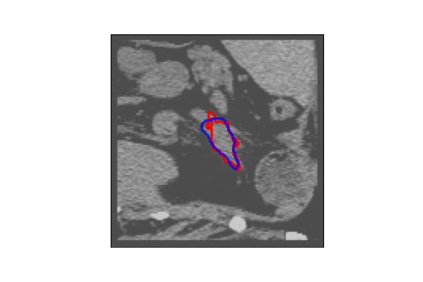

The human annotations are imperfect, especially when produced by junior practitioners. Multi-expert consensus is usually regarded as golden standard, while this annotation protocol is too expensive to implement in many real-world projects. In this study, we propose a method to refine human annotation, named Neural Annotation Refinement (NeAR). It is based on a learnable implicit function, which decodes a latent vector into represented shape. By integrating the appearance as an input of implicit functions, the appearance-aware NeAR fixes the annotation artefacts. Our method is demonstrated on the application of adrenal gland analysis. We first show that the NeAR can repair distorted golden standards on a public adrenal gland segmentation dataset. Besides, we develop a new Adrenal gLand ANalysis (ALAN) dataset with the proposed NeAR, where each case consists of a 3D shape of adrenal gland and its diagnosis label (normal vs. abnormal) assigned by experts. We show that models trained on the shapes repaired by the NeAR can diagnose adrenal glands better than the original ones. The ALAN dataset will be open-source, with 1,594 shapes for adrenal gland diagnosis, which serves as a new benchmark for medical shape analysis. Code and dataset are available at https://github.com/M3DV/NeAR.